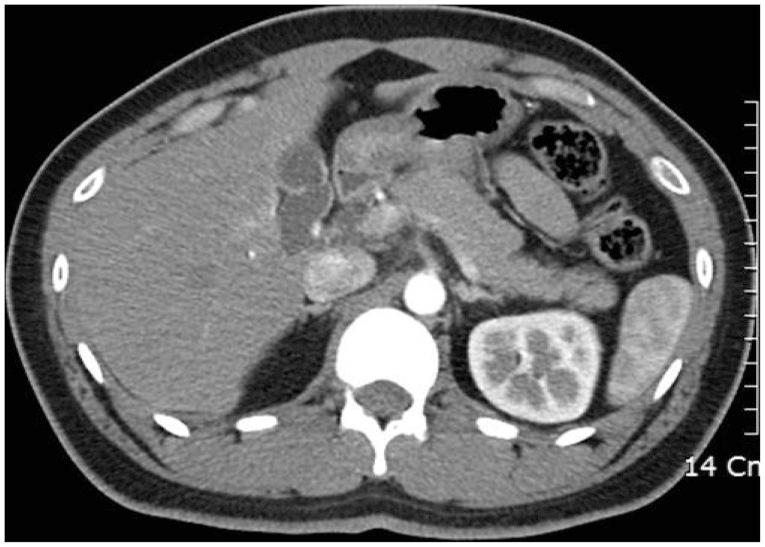

Acute pancreatitis due to a duodenal ulcer.

Duodenal ulcers and acute pancreatitis are two of the most commonly encountered gastrointestinal diseases among the general population. However, duodenal ulcer-induced pancreatitis is very rarely reported worldwide. This report elaborates on a distinct medical treatment that contributes to partial or complete treatment of acute pancreatitis induced by a duodenal ulcer scar.